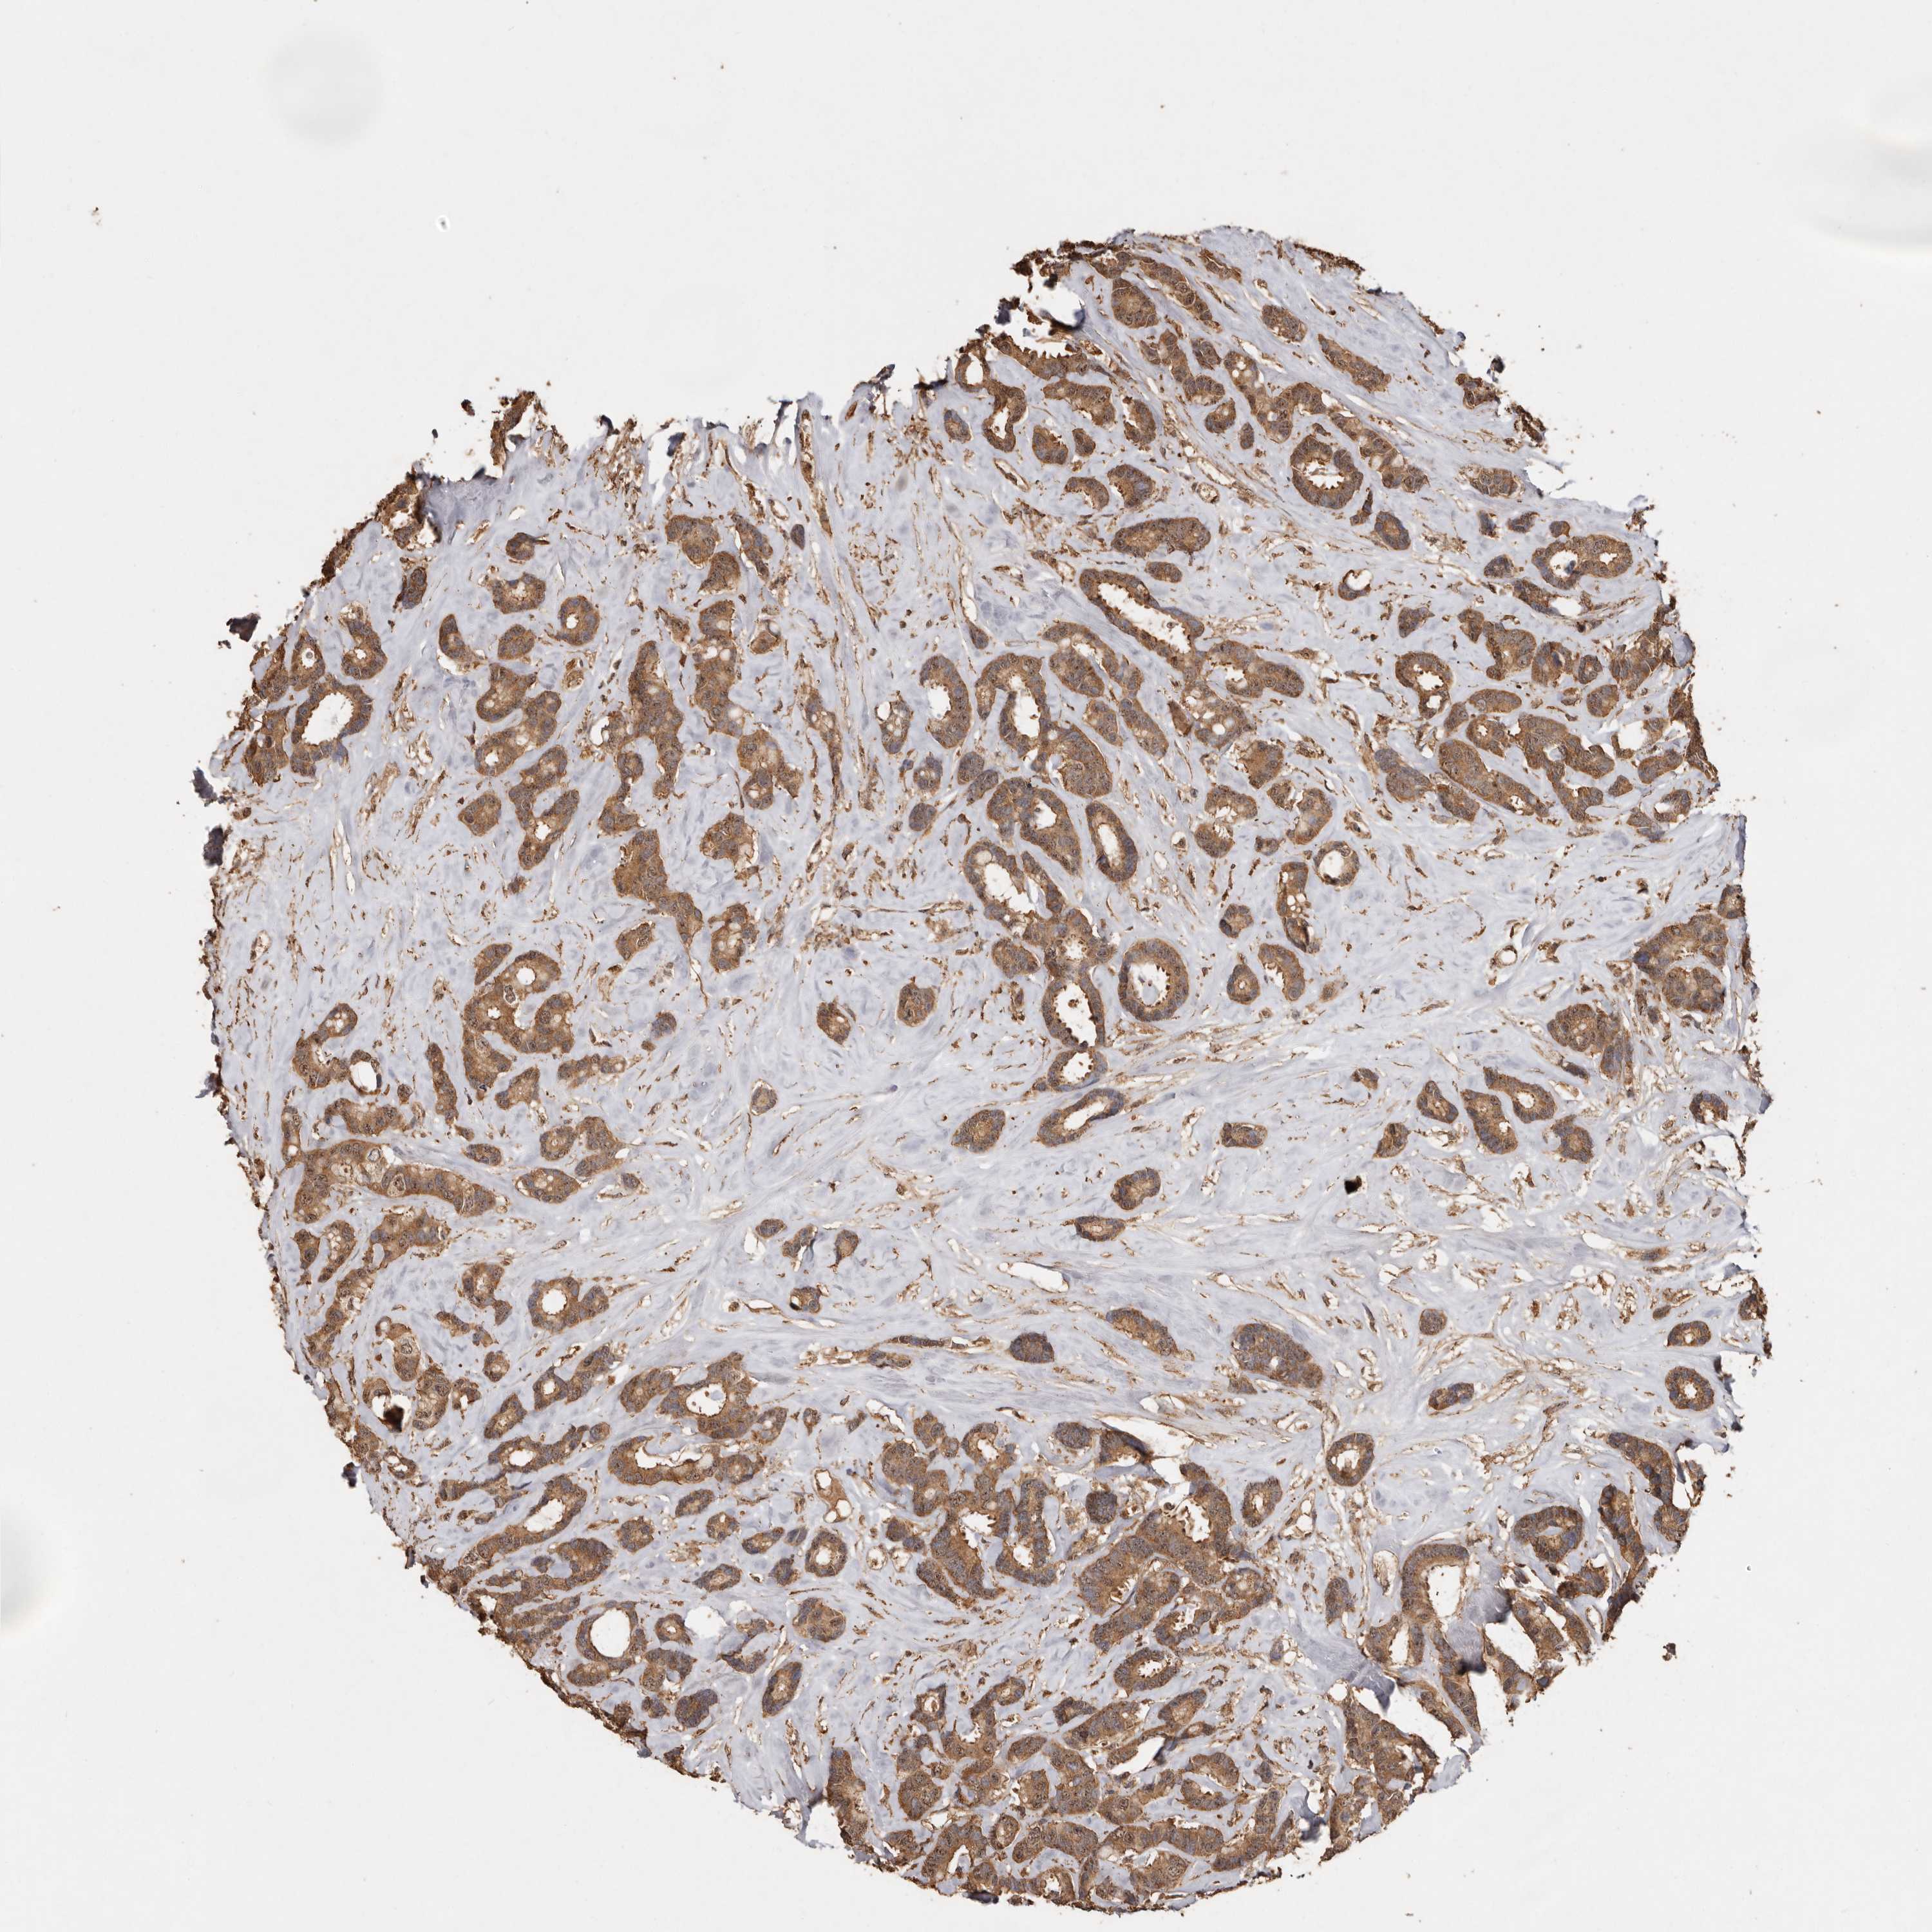

CANCER BREAST CANCER Show tissue menu

BRCA TCGA BRCA VALIDATION PROTEIN EXPRESSION